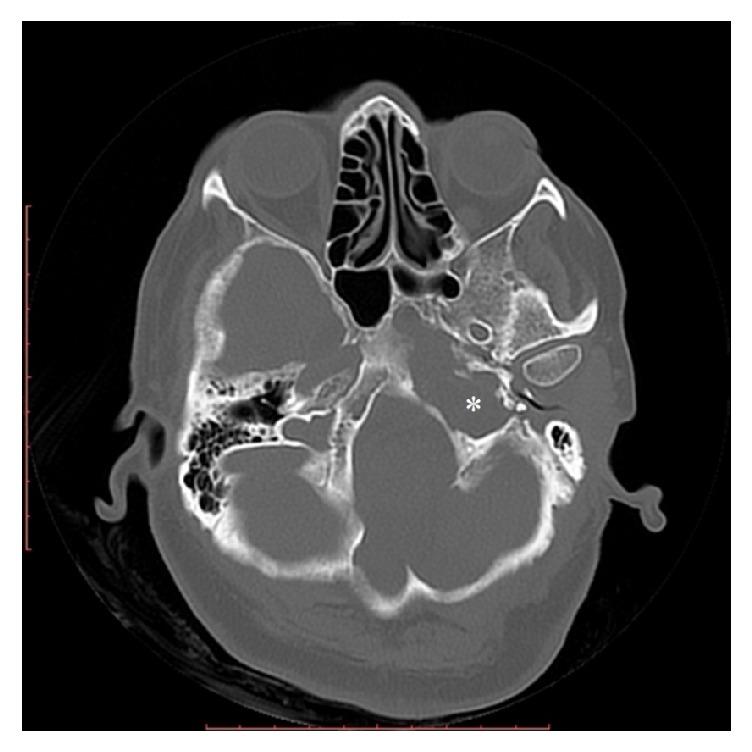

Imaging Findings of Jugular Foramen Meningocele in a Neurofibromatosis Type 1 Patient.

Neurofibromatosis type I (NF1) is a neurocutaneous disorder that involves autosomal dominant transmission. Skull defects, including sphenoid dysplasia and calvarial defects, are a rare finding in patients with NF1. Spinal meningocele and sphenoid wing dysplasia have been identified in NF1 but the occurrence of meningoceles at the skull base is extremely rare. A rare instance of jugular foramen meningocele being identified in an NF1 patient on imaging is described in this paper. To the best of our knowledge, only two such cases have been reported in the English literature.